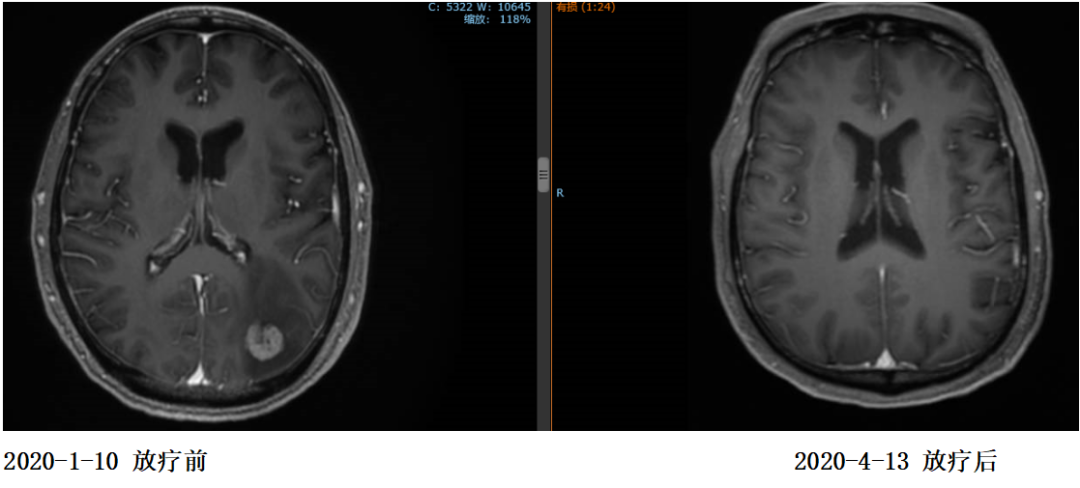

2020年1月13日开始对左侧枕叶及右侧小脑转移灶进行放疗,PTV-GTV=44.5Gy/9F

复查:2020.4复查颈部CT及全腹部+盆腔MR大致同前,脑MR示病变较前明显缩小,评估PR。

2020年11月4日复查颈部胸腹盆CT大致同前,脑转移灶明显缩小,继续赫赛汀联合希罗达维持治疗。